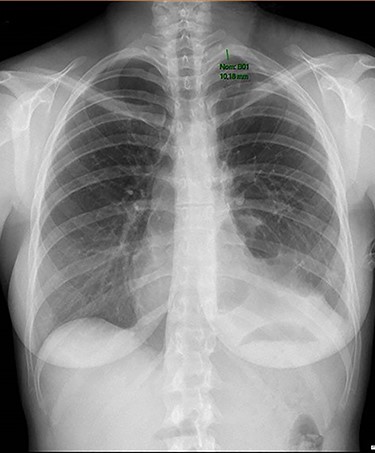

Chest radiography showing small residual pneumothorax after chest tube removal.

The overall surgical time was 159 min. The operation was uneventful. On the 10th postoperative day chest tube was removed (Fig. 2). No complications were noticed besides a prolonged air leak that was treated conservatively.